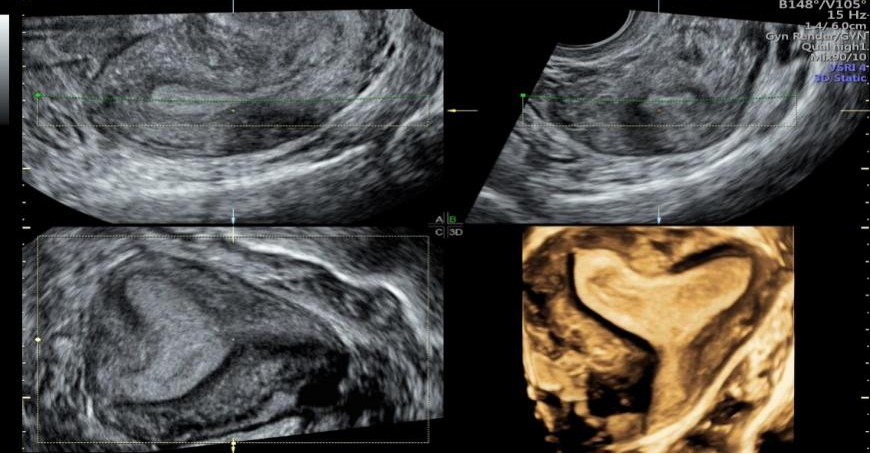

1、胎儿及胎儿附属器的异常检查更卓越

用于胎儿颜面部、 中枢系统及脊柱异常的显示, 通过细致的多切面成像分析胎儿的解剖结构及发育状况。

7、 妇科疾病精准诊断的强大助力

更精准的图像能够对子宫畸形及宫腔病变、输卵管、卵巢、卵泡等进行全面评估;盆底三维四维超声有着多平面成像的优势。